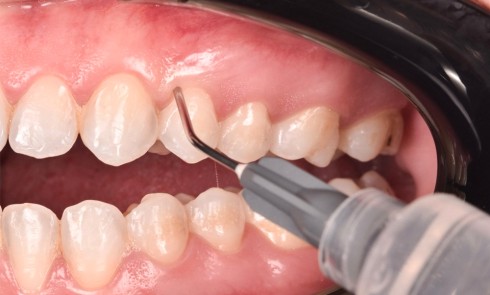

Article réservé à nos abonnés Bridge collé cantilever vs Implant unitaire : analyse décisionnelle, implications biomécaniques et gestion clinique

La gestion de l’édentement unitaire, qu’il soit antérieur ou postérieur, demeure un enjeu quotidien en odontologie prothétique. Ce type de...